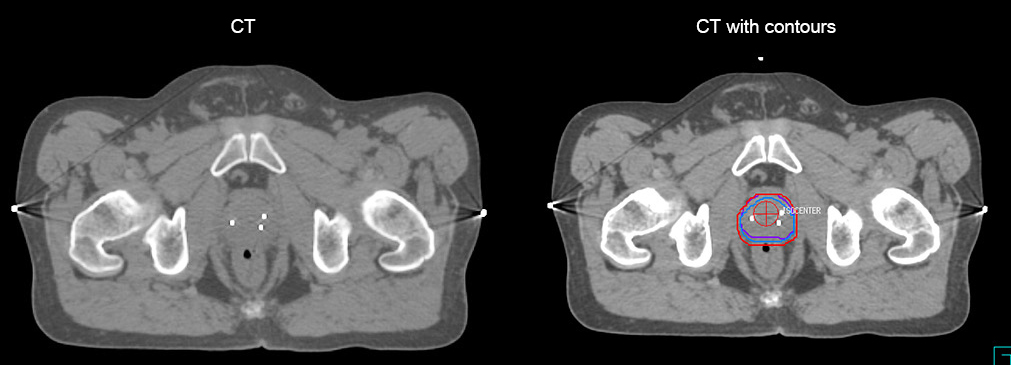

“The biggest problem for CT-based planning, especially in prostate, is you can’t see the cancer very well,” says Dr. Stevens. “On CT it can be quite challenging to see the edge of the prostate especially at the apex. When the edge of the prostate can’t be delineated well on CT, radiation oncologists will increase their margins a little bit so they don’t miss it, but that can also increase toxicity.” “Using MR, the prostate is well delineated. We quickly see the edges of cancerous tumors like in prostate cancer, and as normal structures can be defined, we can optimize the treatment plan to protect these organs and their normal function. This can potentially improve the outcome. And it improves workflow as well. We can contour more quickly, confident that the tumor is going to be in the field.” “The Ingenia 3.0T MR scanner provides high resolution allowing us to make scans fast for the patients. It also gives the potential to include methods like MR spectroscopy and diffusion weighted Imaging, which we’re in the process of doing right now,” Dr. Stevens adds.

“There are some general challenges in RT imaging – even with CT – such as imaging geometry and positioning accuracy. Positioning is extremely important in RT, because we need reproducibility between imaging and treatment position. We also need accurate geometry so we can be sure our treatment plan is properly delivered during the treatment,” says Dr Yan. “The Ingenia MR-RT configuration includes an external laser positioning system for patient alignment and a flat tabletop for imaging the patient in treatment position. Ingenia MR-RT also came with a special QA package for regular monitoring of precision. Our Ingenia 3.0T scanner achieves good geometric accuracy – within a millimeter for most patients – and the phantom measurement is even better,” he adds. “Ingenia’s wide 70 cm bore is valuable to easily accommodate immobilization devices needed in RT,” says Dr. Stevens. “With a small bore MR scanner you can’t get the RT immobilization devices into the scanner properly; the large bore makes it easy to image patients in their immobilization device.”

“When a patient registers, first CT simulation and MR simulation are done, followed by CT-MR registration on Pinnacle3. Then the target and normal organ delineation is performed on MR images. Meanwhile we create a reference CT image for online treatment and localization correction. During the treatment phase we can perform additional MRI scans to visualize the anatomy changes and create an adaptive plan. This plan basically adapts the treatment plan to the changes.” “Along with its great benefits, MR has introduced some new challenges,” Dr. Stevens says. “Radiation therapy teams generally have no experience with MR. The Philips training helped us to implement fully the things we can do with the Ingenia MR-RT system. So the training, as well as having a good MR physicist, is critical.”